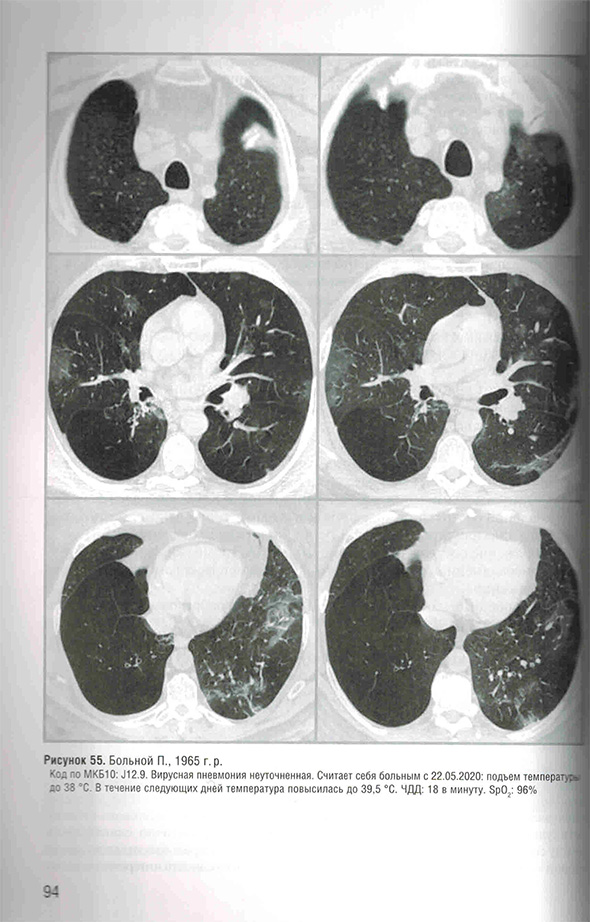

Протокол «Вирус-ассоциированного поражения легких: COVID-19, динамика»